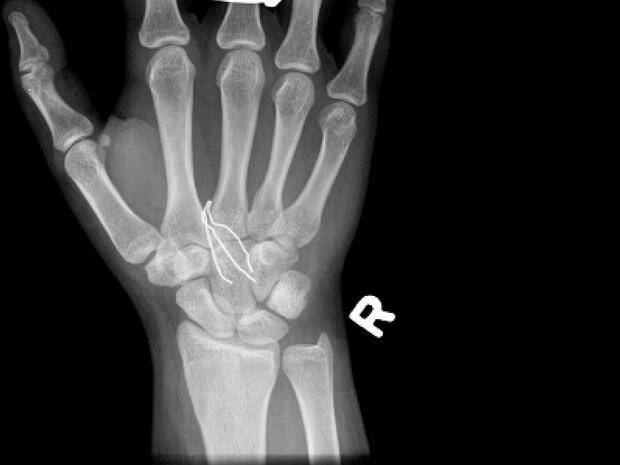

Niektórym osobom, zwłaszcza w wieku nastoletnim, trudno jest się powstrzymać od umieszczania rzeczy pod swoją skórą. Lekarze twierdzą, że rośnie liczba nastolatków – zwłaszcza z depresją lub lękami – które wbijają igły, zszywki, spinacze oraz inne przedmioty pod skórę swojego ciała. Tę dość bezkrwawą praktykę lekarze nazywają czasem “zachowaniem samo-osadzającym” lub “zagnieżdżającym”.

Samookaleczenia są niebezpieczne – oprócz ryzyka wywołania infekcji, umieszczanie w ciele przedmiotów może uszkodzić nerwy lub naczynia krwionośne. – W skrajnych przypadkach oprócz krwawienia (w tym wewnętrznego) może wystąpić nawet udar – powiedział Shiels.

– Jeśli dasz niektórym z tych dzieciaków magazyn do poczytania, to odzyskasz go z brakującymi zszywkami – mówi Shils. – Daj im ołówek, a wyciągną grafit i wsadzą do pod skórę.